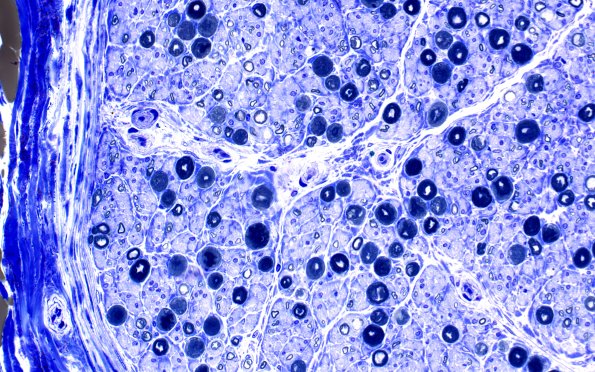

Washington University Experience | PERIPHERAL NEUROPATHY | 9B PERINEURITIS & PERINEURIAL PATHOLOGY | 3E3 Perineurium hyperplasia case (Case 3) Plastic 40X 3

Toluidine-blue stained sections showed mild crush artifact and patchy loss of both large and small axons. Clusters of small axons as well as axons with myelin sheaths which are thin for axonal caliber, both indicative of a cycle of degeneration/regeneration, are present. One fascicle shows nearly complete replacement by thinly myelinated axons. ---- Not shown: CD20 and CD3 show no significant increase in background B-cells or T-cells in the fascicles. CD68 immunoreactivity shows no significant increase in macrophages within the wall of the fascicle with perineurial hyperplasia. ---- Comment: The microscopic findings are those of a neuropathy with moderate patchy loss of large and small axons. The single fascicle undergoing perineurial hyperplasia is very unusual. This fascicle does not exhibit classic perineuritis, in that there is almost no inflammation or macrophage accumulation within the perineurium. We wondered if the patient had previously received steroids but could not find a history of it.